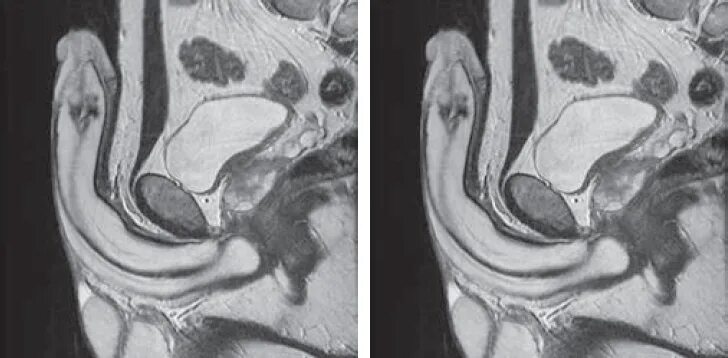

Аномалия полов орган